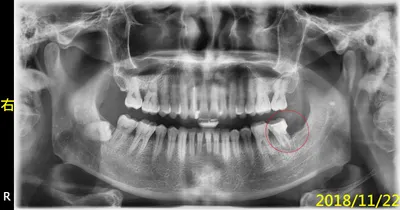

說明『根管治療後,不做牙套,是多麼的危險,會導致前功盡棄(保留牙齒廢物利用,不要拔牙)』,何況他還要先做『牙冠增長術』....所以,為了幫智齒擦屁股、收拾爛攤子,您看事後要付出多大的代價....他後來當然就自動消失啦,去找願意幫他便宜處理的所謂良心牙醫啦,只不過,撐不到一年,他就又回來找我啦....